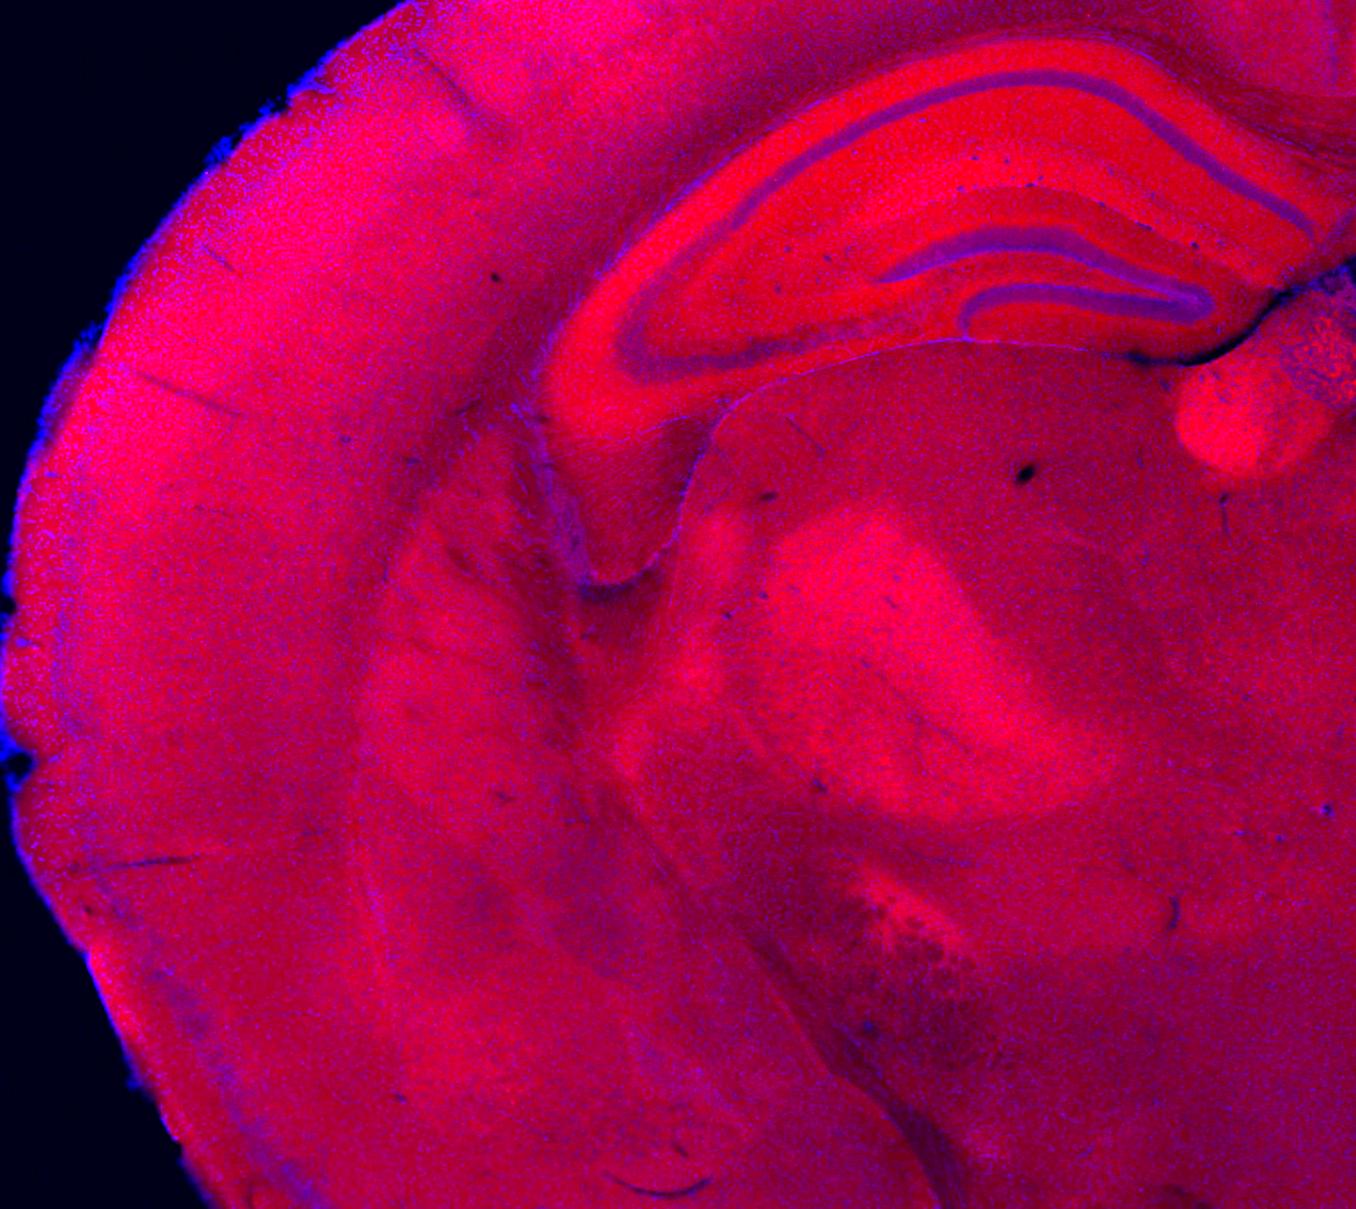

The cover of this year’s program features an image from a study published in The Journal of Neuroscience by scientists at the UC Irvine Center for the Neurobiology of Learning and Memory. The image shows a coronal section of a mouse brain, captured using fluorescence microscopy. In this technique, specific molecules are tagged so they emit light when excited under a microscope—here, the protein MDGA1 is shown in red and all cell nuclei are shown in blue—allowing scientists to map where proteins are expressed across different brain regions.